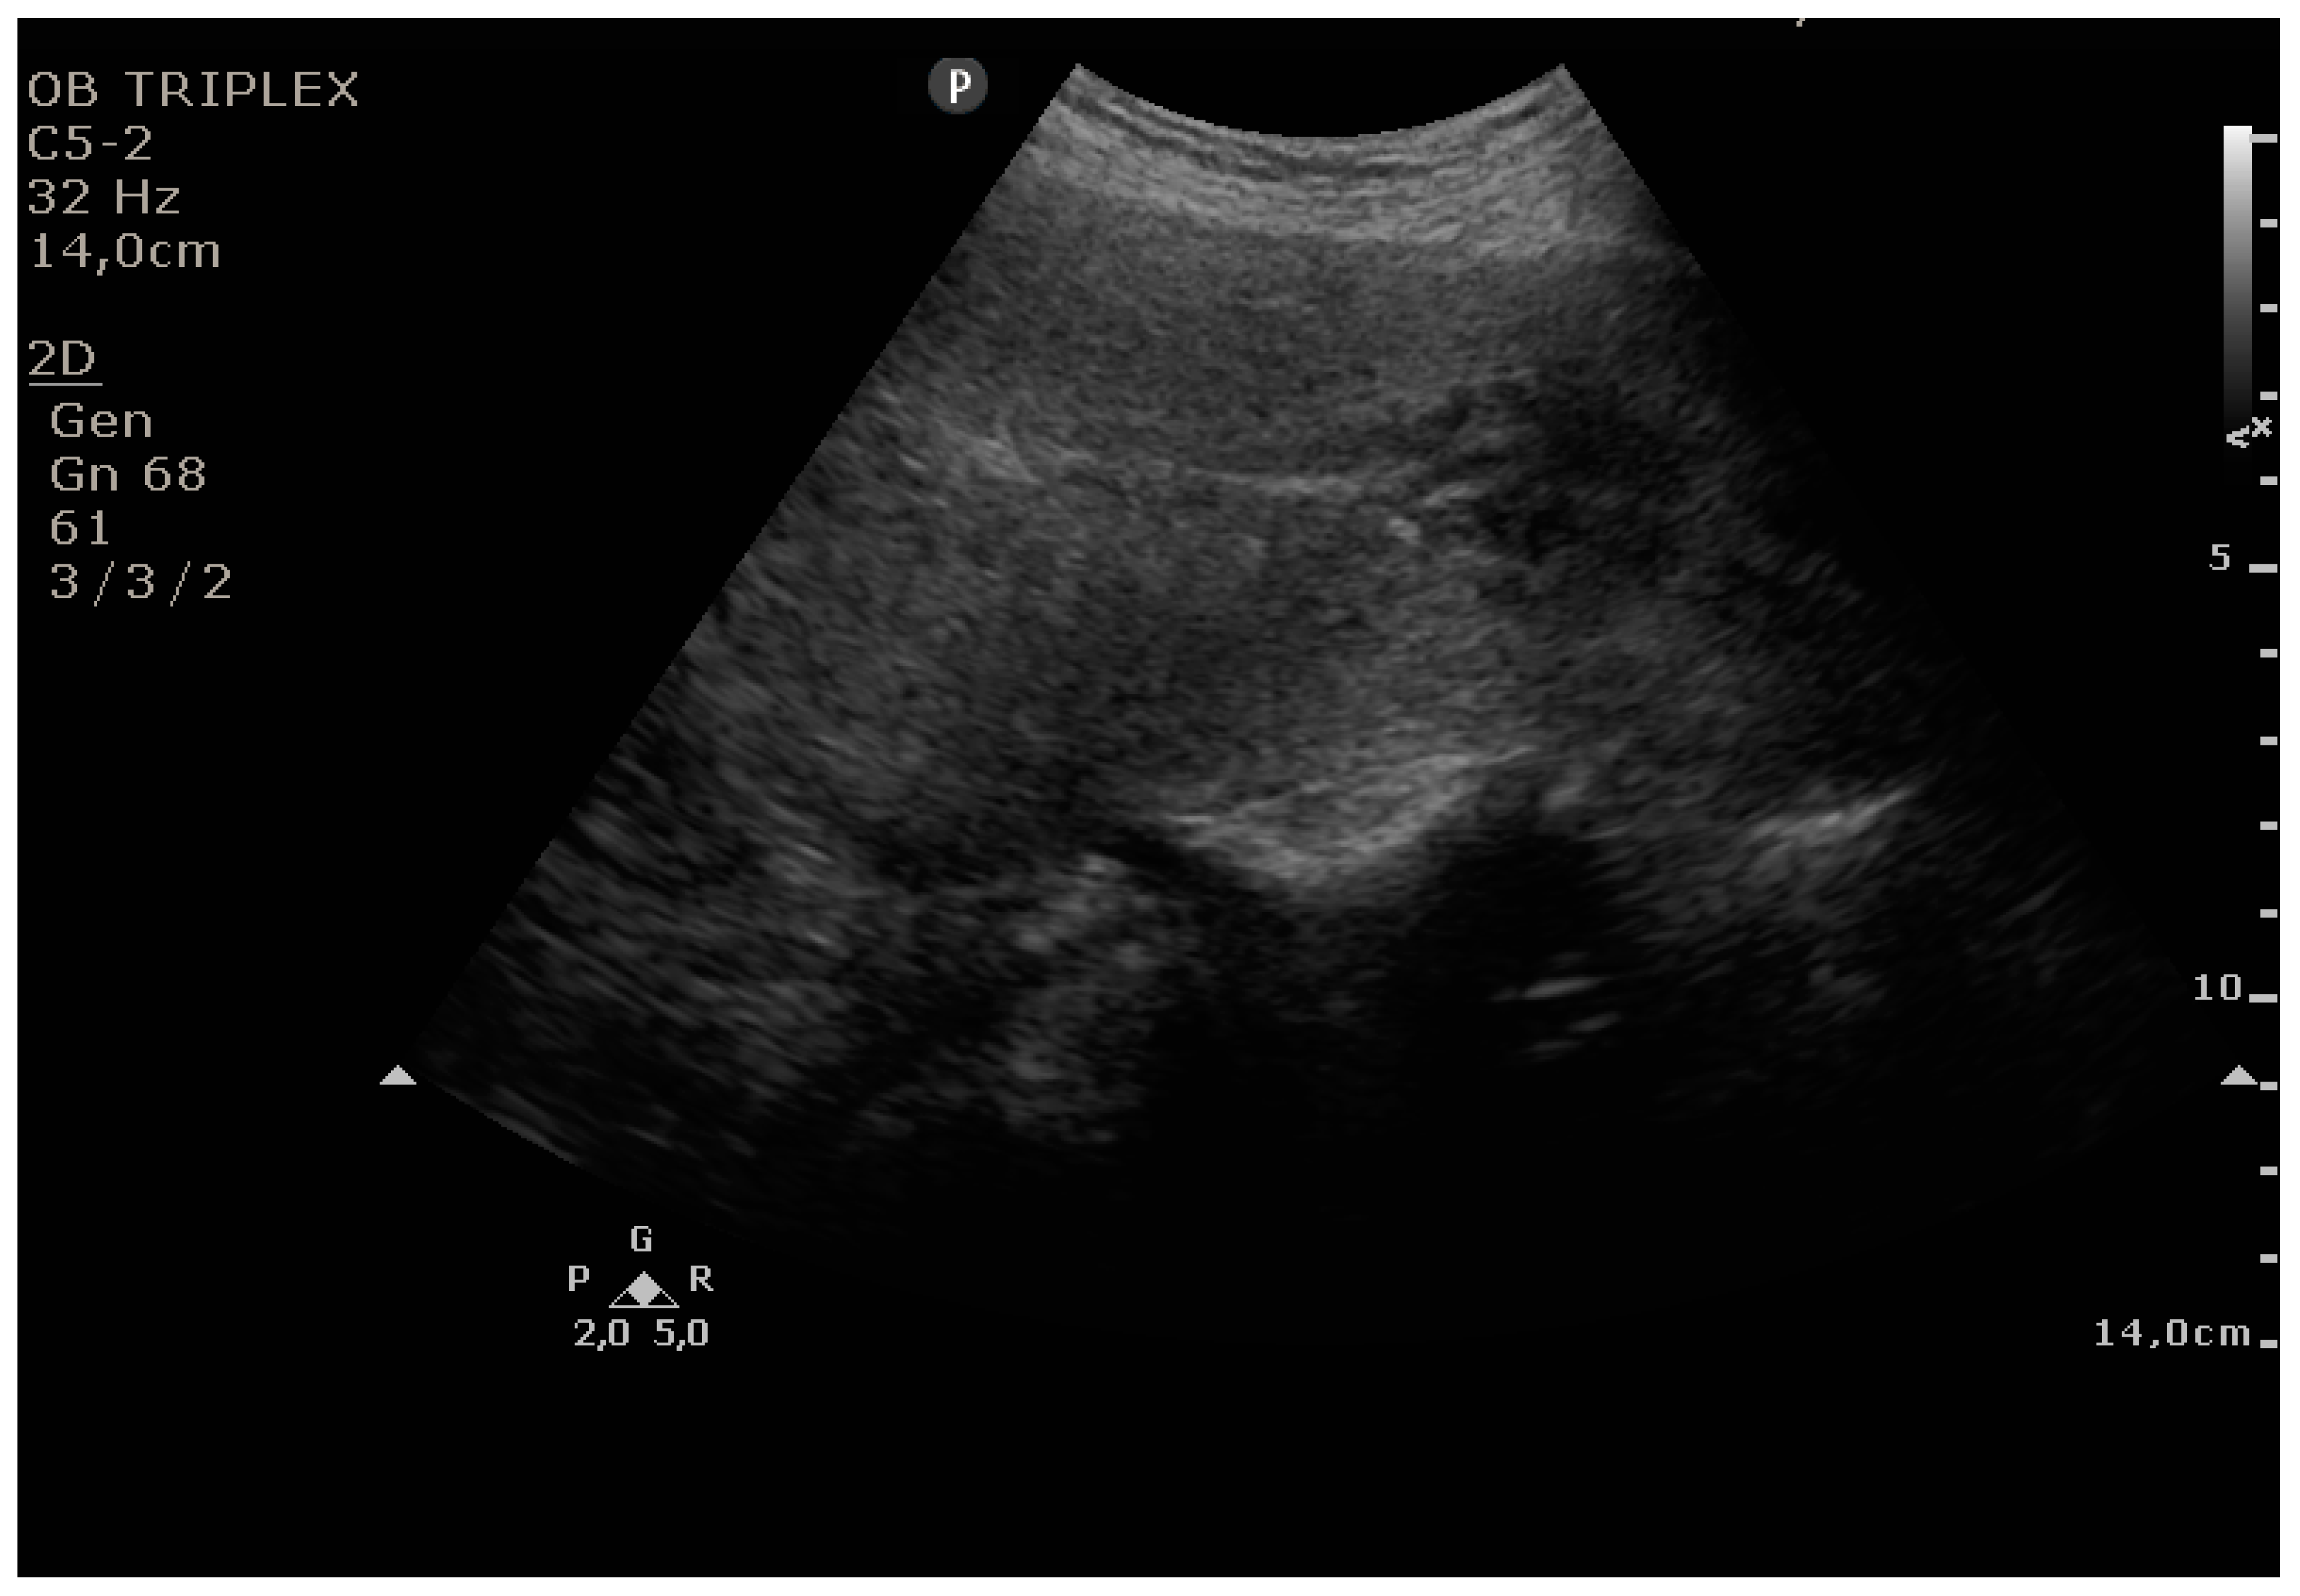

The PUUS method evaluates the proportion of the endometrial length occupied by blood or debris, as follows (Figure 1, Figure 2, Figure 3, Figure 4 and Figure 5):

Figure 3.

Grade 2: less than one-half of the endometrial length occupied by blood or debris.